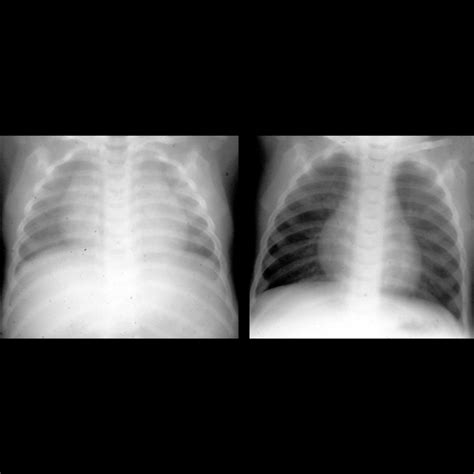

• X-rays: Often the first line of defense for bone fractures or lung issues.

X-ray Minimal Bone fractures, pneumonia, chest congestion